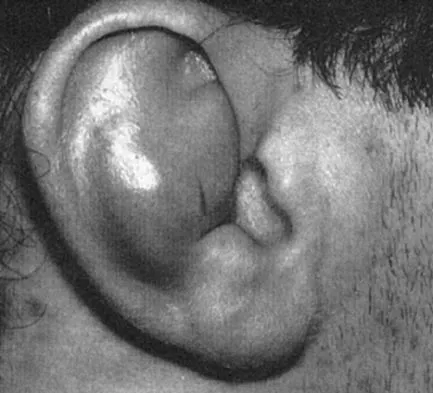

Figures 11a and 11b show the AP and lateral radiographs of a 32-year-old patient on hemodialysis who has increasing elbow pain and a visibly growing mass over the extensor surface. Figure 11c shows the photomicrograph of the biopsy specimen. What is the most likely diagnosis?